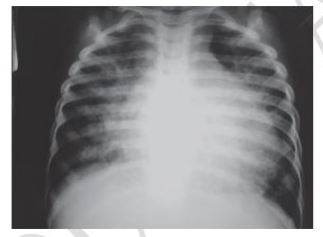

Lactente, 1 ano e 8 meses, trazido ao pronto-socorro, pois há 1 dia apresenta desconforto respiratório e irritabilidade. Ao exame físico: REG, sudorese profusa e palidez; murmúrio vesicular + em ambos hemitóraces, com estertores difusos; frequência respiratória: 60 incursões/minuto, saturação de O²: 95%, em ar ambiente, repouso, com tiragem subdiafragmática e intercostal. Bulhas rítmicas, normofonéticas, sem sopros, frequência cardíaca: 178 batimentos/minuto. Abdome: plano, depressível, indolor à palpação, com fígado palpável a 4cm do rebordo costal direito. A mãe relata que há 2 semanas a criança apresentou rinorreia, obstrução nasal e febre. Você solicita a radiografia de tórax, reproduzida a seguir. Qual é a hipótese diagnóstica para o caso?

- A) Pneumonia aguda.

- B) Miocardite viral aguda.

- C) Bronquiolite viral aguda.

- D) Síndrome gripal.

- E) Kawasaki incompleto.